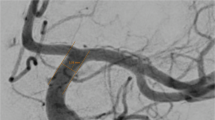

The proposed automatic novel adaptive segmentation algorithm obtained a DSC of ~92.23%, a sensitivity of ~94.82%, a specificity of ~99.00%, and an AVVD of ~10.00% in delineating cerebral blood vessels compared to the manually segmented ground truth. These results demonstrate the high accuracy and efficacy of this algorithm. Figure 7 shows an output instance of the segmentation algorithm. To highlight the accuracy enhancement of the proposed approach over existing methods, a comparison to the global statistical approach24 was conducted and the results are shown in Table 2. Figure 8 shows sample 3-D segmentation results for three MRA subjects along their maximum intensity projection (MIP). These qualitative results demonstrate how the proposed segmentation approach is capable of obtaining fine details of the brain vasculature.

Sample output of the local adaptive segmentation algorithm: (a) Original (raw) image, (b) After bias-correction, (c) After GGMRF-enhancement, (d) Distance map and iso-surfaces generated, (e) Subsurfaces-based extraction of brain tissues, (f) Final delineated cerebrovasculature (h) Initial LCDG global segmentation, (i) Results after applying the proposed local adaptive segmentation from the same plane, (j) and preceding and succeeding planes, and 3-D visualization of results using a growing tree model (k–m).